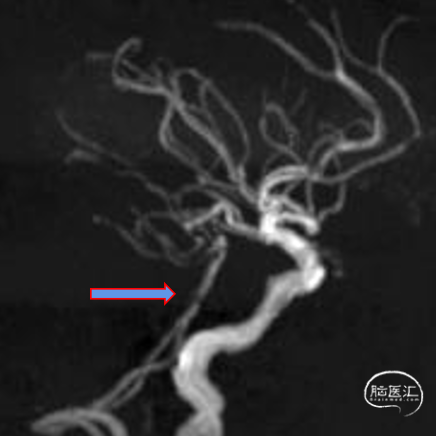

椎动脉后循环旋转造影

造影示:右侧优势椎,经右侧椎动脉导弯造影,双侧胚胎型大脑后动脉。

椎动脉V2、V3段迂曲,若不建立良好通路,则后续球囊支架无法到位释放。